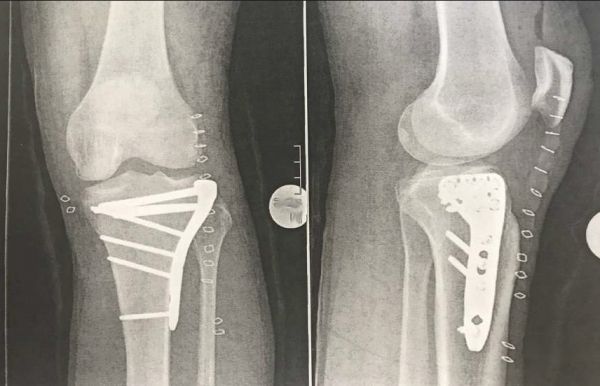

Интересно как сработал Тай Инь - вначале травмотология скрывала от общественности поступление к ним такой известной, особенно в мужском мире, телезвезды и в интервью только подтвердила факт доставки с гоночной трассы неизвестного потерпевшего. Многочасовая операция на левое колено прошла успешно - стальная пластина была зафиксирована шестью винтовыми стержнями, что хорошо видно на рентгеновском снимке.